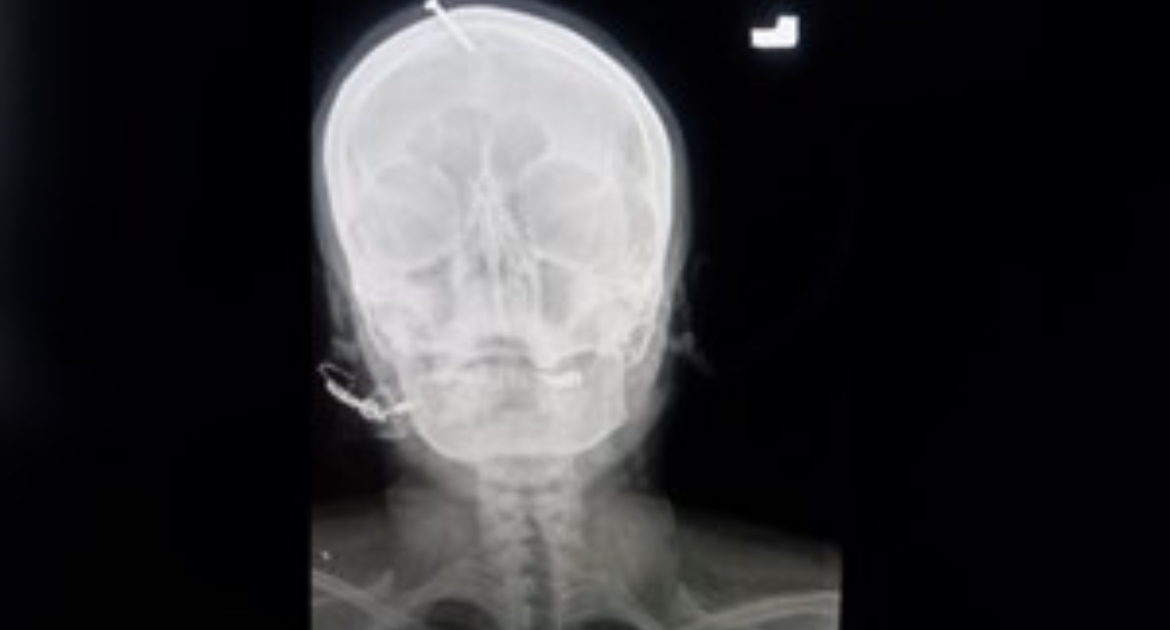

Una radiografía mostró que el clavo había sido clavado cinco centímetros en el cráneo, sin llegar al cerebro.